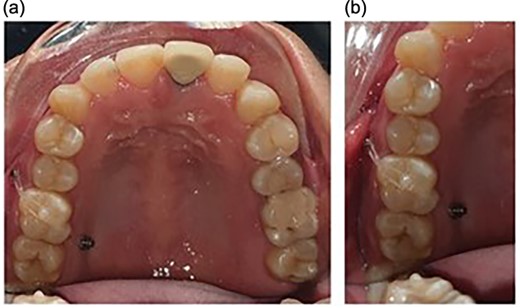

Orthodontic miniscrews measuring 1.6 mm in width and 8 mm in length, respectively, were placed. The screw on the buccal aspect was placed between the maxillary first molar and second premolar, and the one on the palatal aspect was placed between the first and the second molar (Fig. 1). The placement of the screws was planned in order to have a diagonal coverage of the occlusally directed forces for intrusion.

Placement of the miniscrews: (a) on the buccal side between the second premolar and the first molar and (b) on the palatal side between the first and the second molars; composite button on the occlusal surface to direct the forces along the long axis.